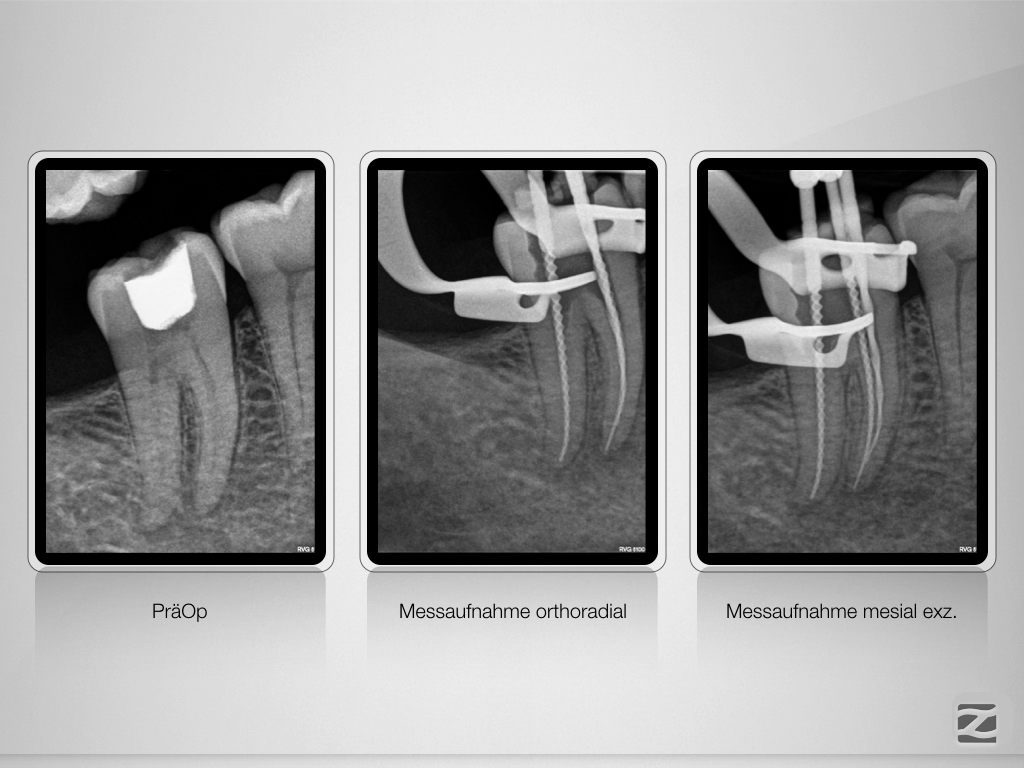

46D.011 Veröffentlicht 27. November 2019 am 1024 × 768 in Sensibilitätsstörung nach Initialbehandlung